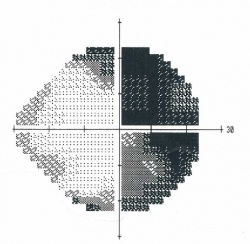

![]()

Figure 1. Humphrey visual field 24-2 showing a bitemporal hemianopsia.

Figure 2. Goldmann visual field showing a bitemporal hemianopsia.[38]

Chiasmal Field Deficits

Characteristically lesions at the level of the optic chiasm produce a bitemporal hemianopia. Pituitary adenomas, which grow upward from the pituitary stalk, compress the chiasm from below, which preferentially involves the inferior, nasal, and macular nerve fibers. This corresponds to superior, bitemporal, and central vision loss. While these field defects typically respect the vertical midline, pituitary adenomas large enough to cause compression tend to also reduce visual acuity and cause diffuse central depression on automated and Goldmann perimetry.[5] Vison loss due to compression first affects the superotemporal visual fields, then inferotemporal, inferonasal and finally superonasal fields.[31]